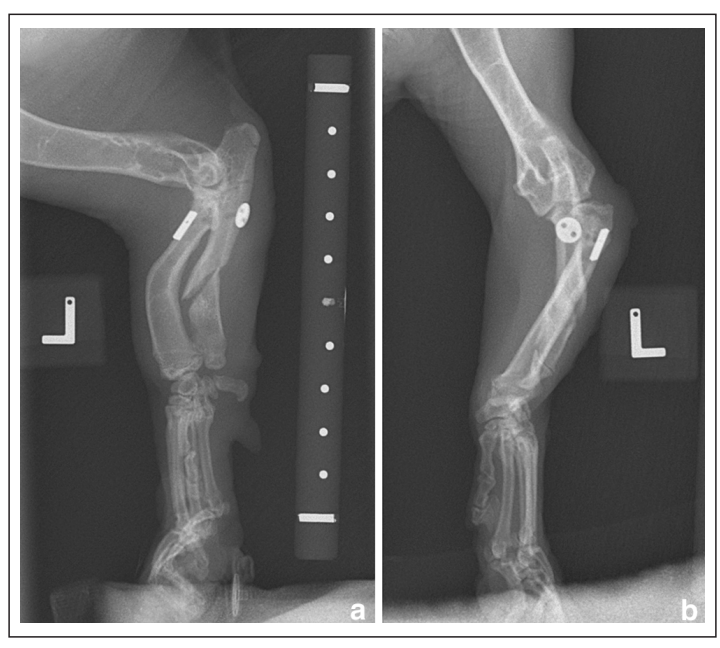

术后6周,行走良好,坐下时左前肢向前伸展,肘关节正常屈曲,这自跛行急性发作以来从未出现过。临床检查发现偶尔抬腿,跛行评分为1/10。与术前状态相比,触诊时桡骨头主观上不那么突出,左肘关节活动范围良好。此时拍摄的X光片(下图)证实桡骨头半脱位的位置与之前的术后X光片相似,并且截骨处有愈合的迹象。

↑ (a) 左前肢术后6周的正侧位和 (b)头尾位X光片。切换针和按钮的位置保持不变。骨痂已经形成,并开始桥接尺骨截骨间隙。桡骨头仍存在持续的外侧半脱位。